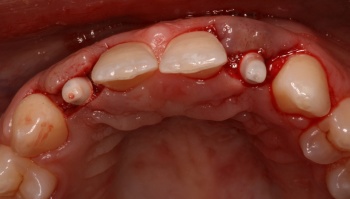

Minimally Invasive Tuberosity CTG for Phenotype Modification:

Rationale for Esthetics and Prevention of Complications

A Case Presentation by Eduardo Lorenzana DDS, MS (San Antonio, TX)